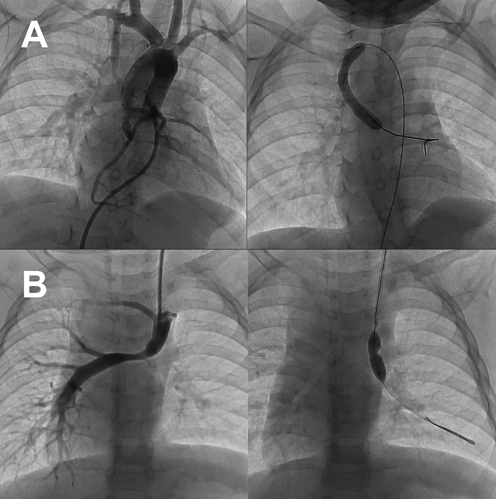

Fig. 2 Different accesses to stenotic lesion for transcatheter balloon angioplasty are shown. Upper panels (A) show balloon angioplasty for a narrowing shunt via the antegrade approach in a patient with tetralogy of Fallot having an aortopulmonary shunt. The catheter is placed from the femoral vein, via the right ventricle, the aorta, and an aortopulmonary shunt, to the left pulmonary artery. Lower panels (B) show balloon angioplasty for the occluded left pulmonary artery in a patient after the bidirectional Glenn procedure. The catheter is placed from the left jugular vein to the left pulmonary artery.

適応決定は圧較差と形態に主眼を置き,肺動脈狭窄では右心減圧あるいは肺血流左右不均衡の是正が目的となる1, 11).先天性心疾患,心臓大血管の構造的疾患に対するカテーテル治療ガイドラインに準じ,有意な末梢性肺動脈狭窄や一次治療としてステント留置が選択できない体格の小さい患者の肺動脈狭窄に対して適応とし(推奨クラスI,エビデンスレベルB),(1)肺動脈主幹部で右室収縮期圧/左室収縮期圧≧2/3,(2)圧較差15~20 mmHg以上,(3)造影による形態的狭窄,を治療適応とする1).ただし,(2)の圧較差を指標とする場合,片側末梢性肺動脈狭窄では健側肺が代償するため圧較差が病状を正確には示さない可能性もあることを考慮し,造影による形態的狭窄率を加味して適応判断するが基準はない.Fontan・Glenn術後等の右心バイパスでは肺循環改善を目的とするため前述ガイドラインによらない積極的な経皮的バルーン血管形成術を推奨する意見もある12–14)